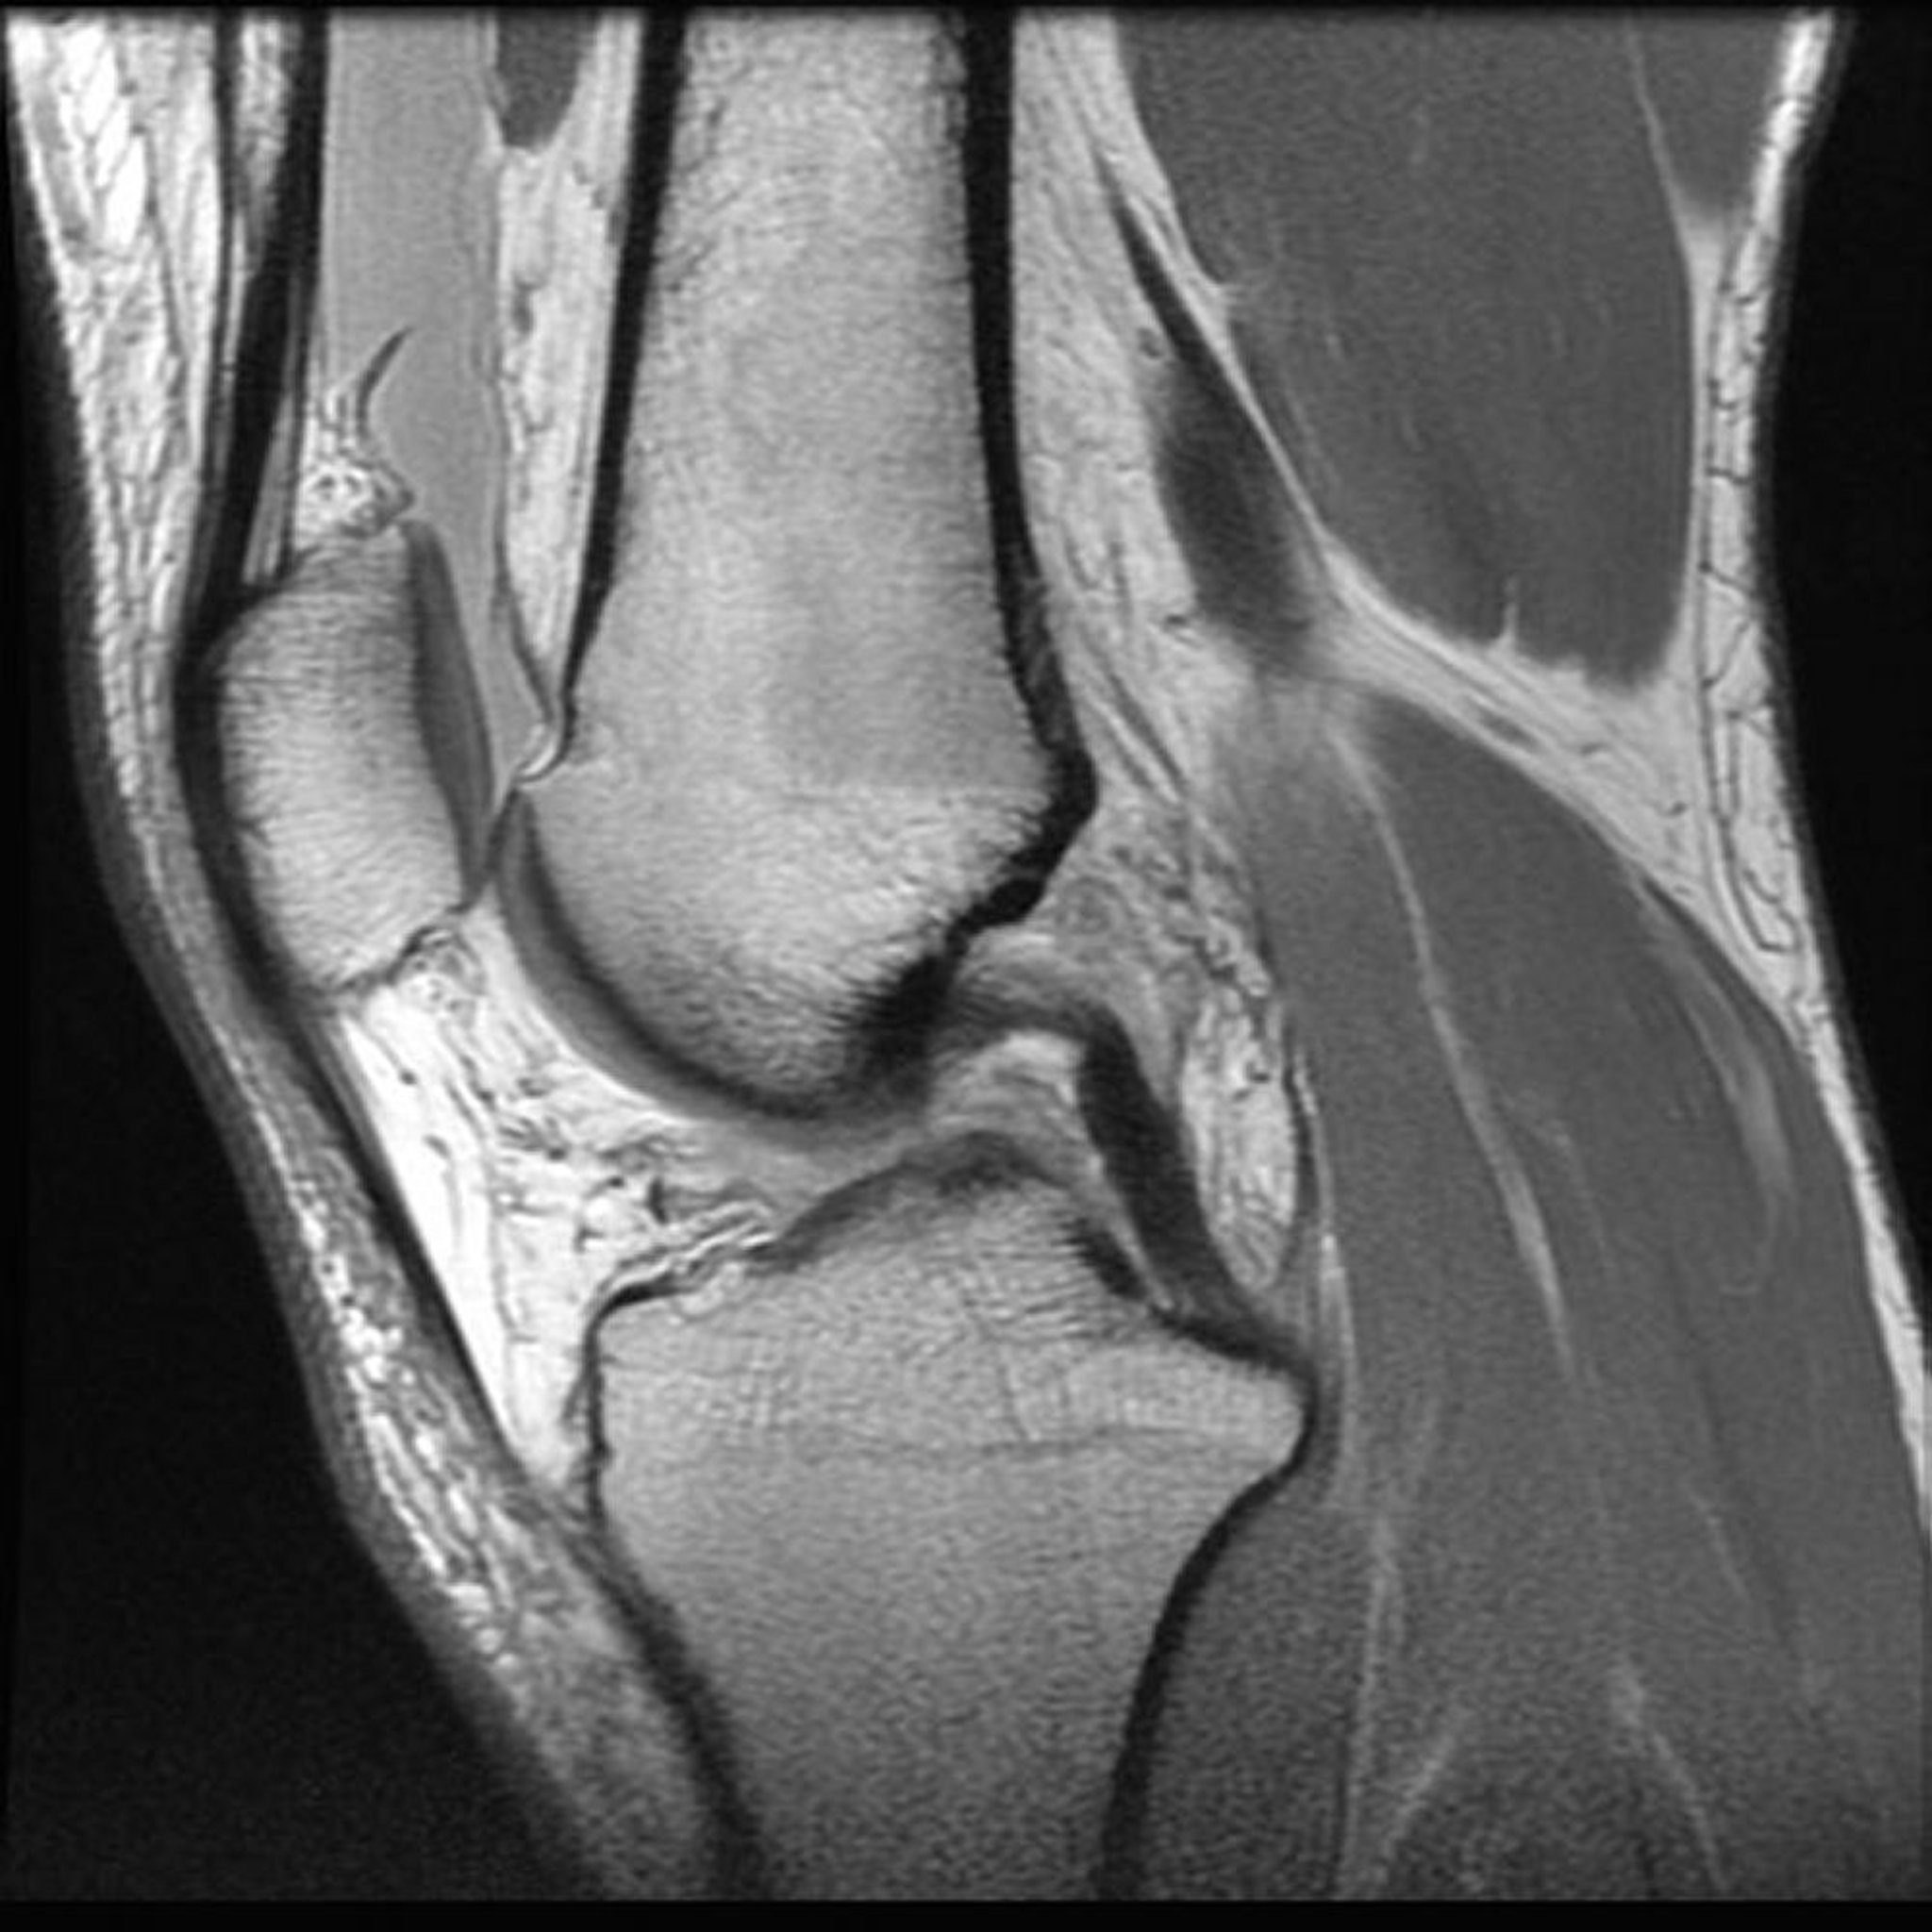

Магнитно-резонансная томография (МРТ) коленного сустава

Фотография предоставлена д-ром Джоном А. Якобсоном (Jon A Jacobson).

Магнитно-резонансная томография (МРТ)